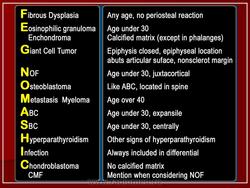

Дифференциальная диагностика изображения